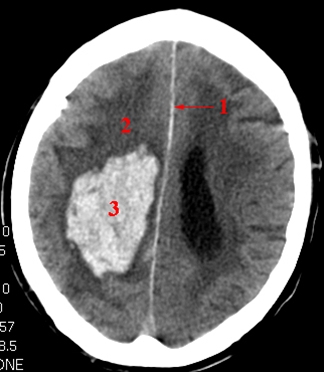

CT skanning af cerebrum.

Blødning (lyst område) i hjernen på patientens højre side. Der er let omgivende ødem (mørkere) og diskret forskydning af midtlinjen. Blødningens placering er typisk for en hypertensions associeret blødning.

1. Falx cerebri

2. Ødem

3. Blødning